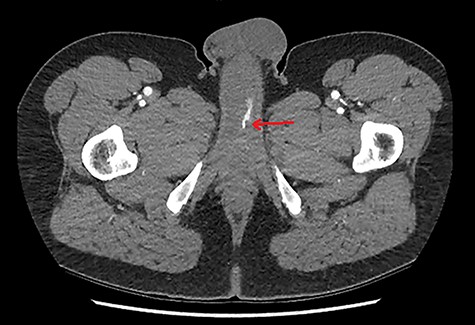

A 28-year-old gentleman presented with a non-tender, persistently rigid penis 2 weeks after a blunt force injury to his perineum. There was no penetrative damage or other symptoms, with an unremarkable background medical history. Pain-free and well, initial investigation with Doppler ultrasound (US) was sought. US demonstrated some hypoechoic tissue within the corpus cavernosum, but otherwise there was no other soft-tissue abnormality. Colour Doppler did however find an abnormally low peak-systolic-velocity (PSV) in the left cavernosal artery. As such computed tomography angiography (CTA) was arranged, showing an asymmetrical arterial-phase blush within the proximal portion of the left corpus cavernosum, neighbouring the left cavernosal artery (Figs 1 and 2). With no other radiographic genitourinary abnormality, HFP was diagnosed, secondary to arterial pseudoaneurysm.

CTA demonstrating an axial view of contrast enhancement within the region of the left cavernosal artery, indicative of an arterial pseudoaneurysm (red arrow).